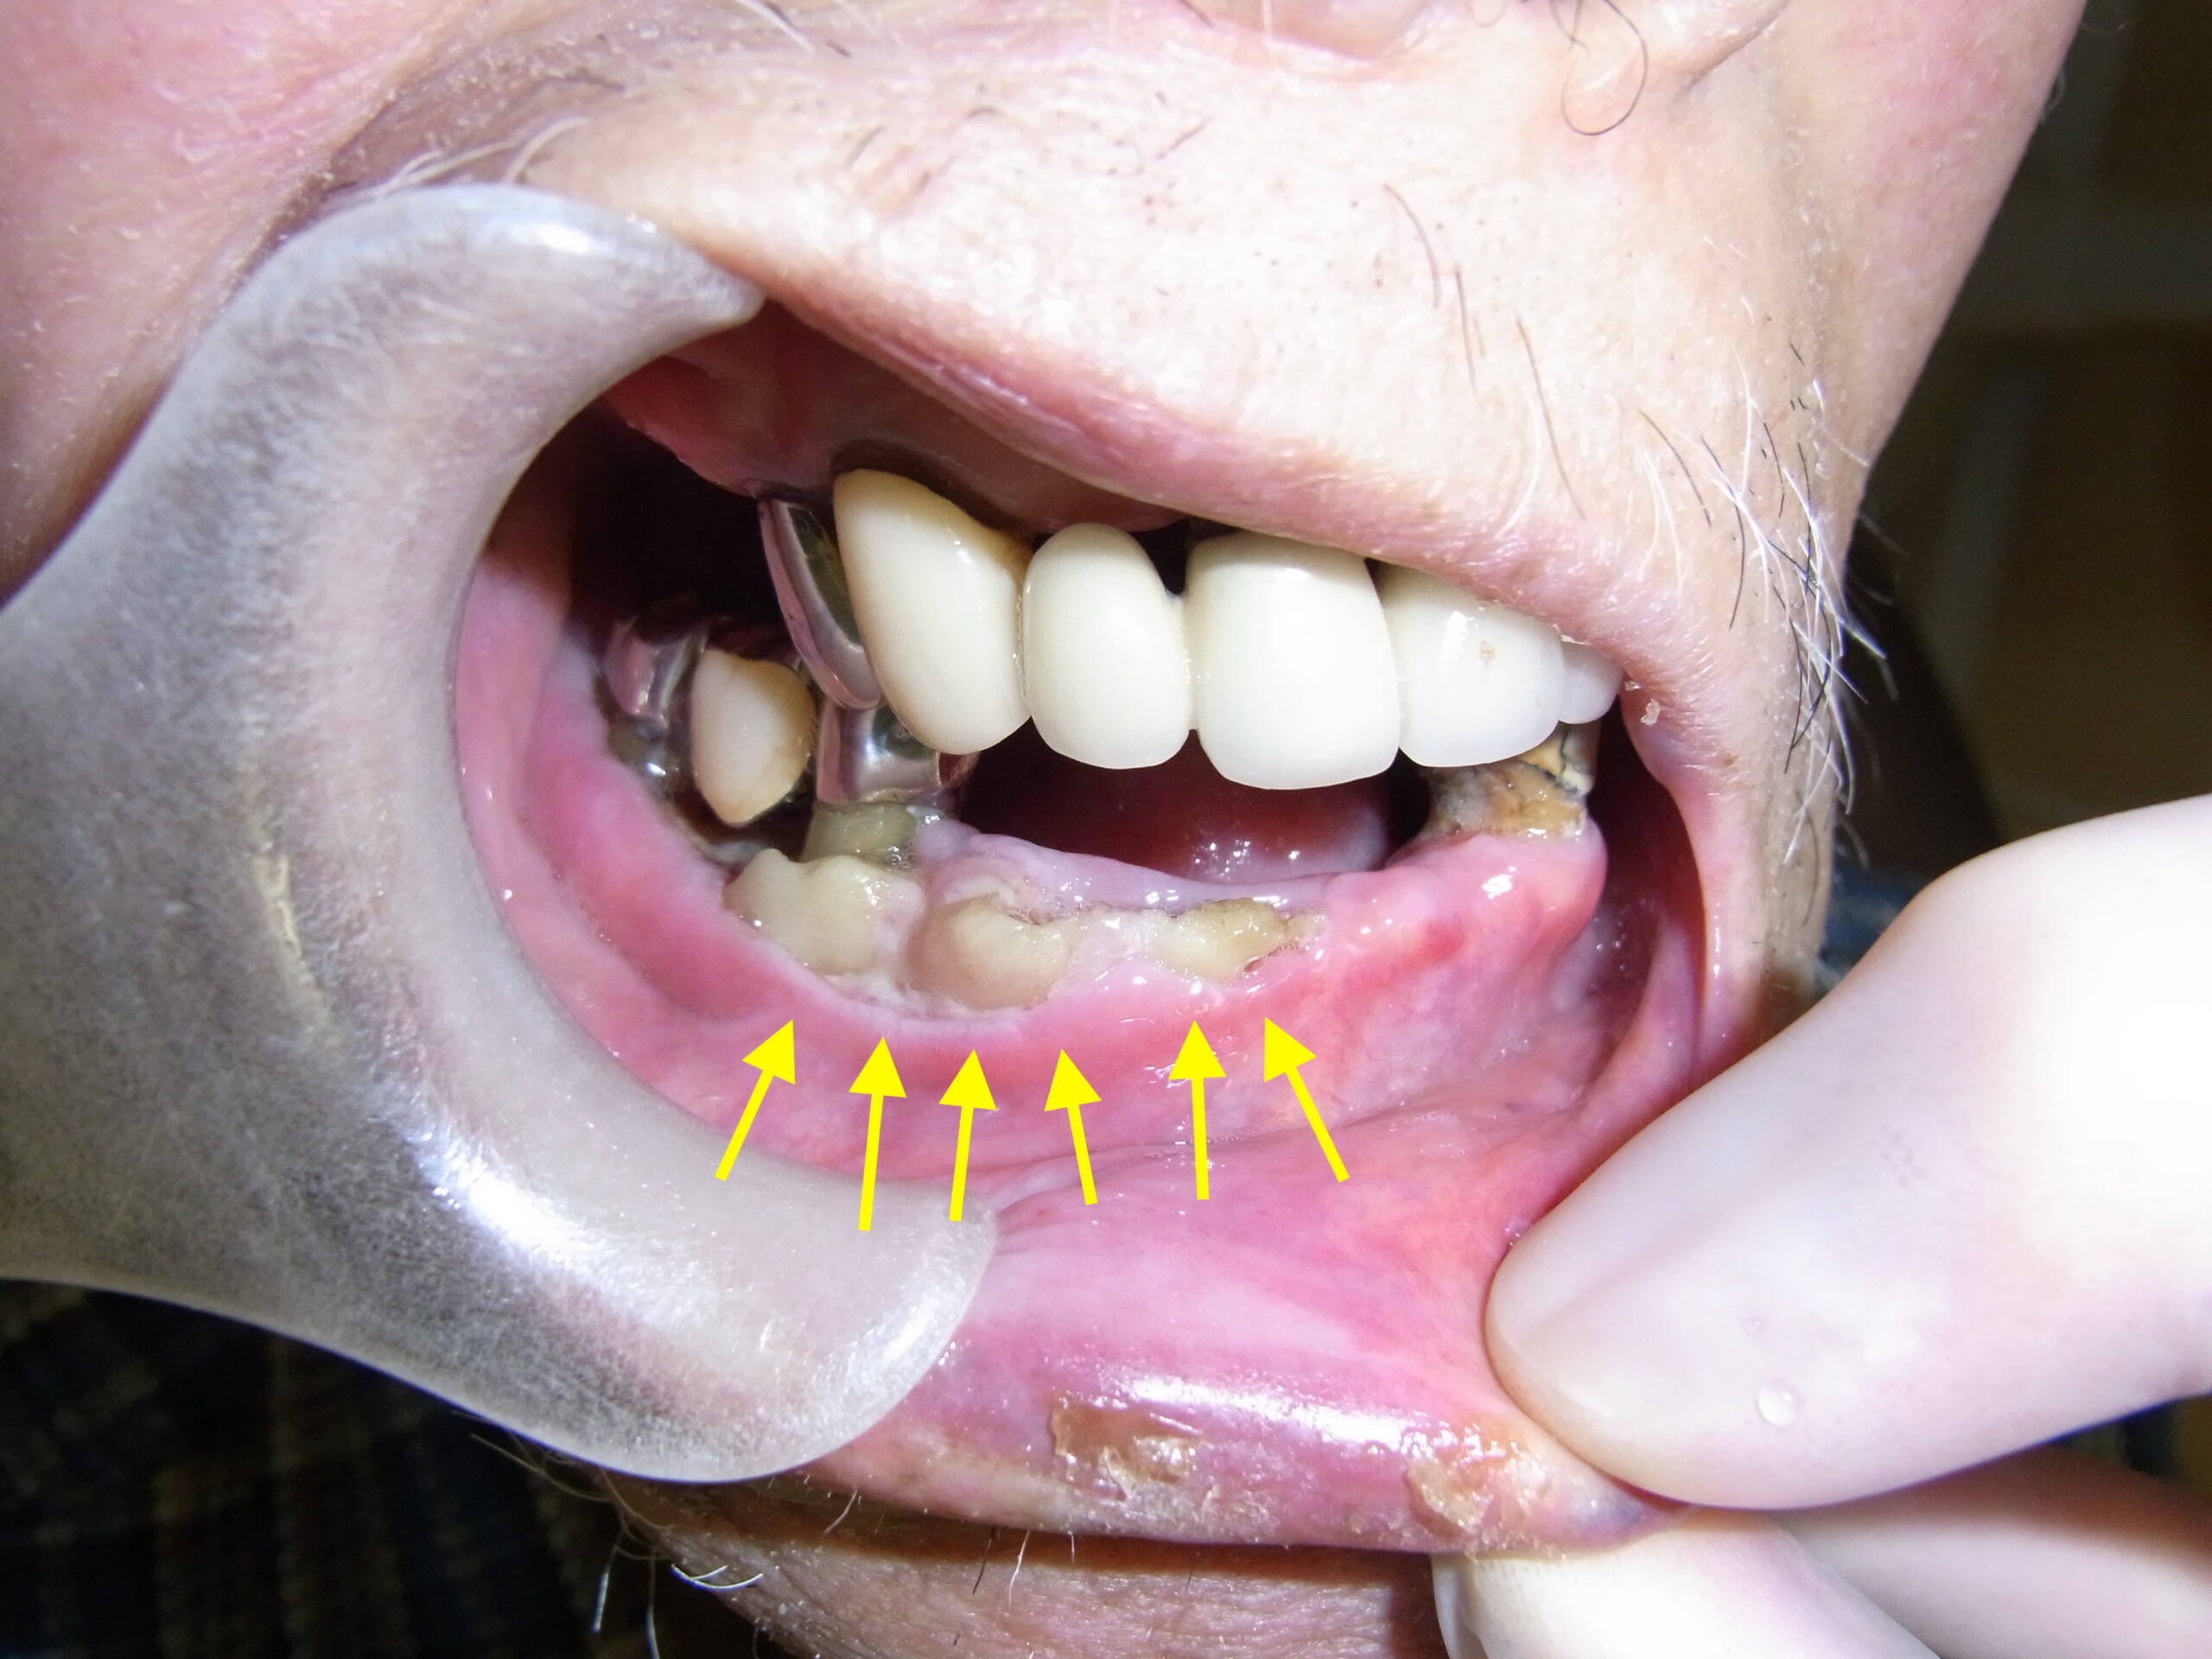

皆さん、「口唇ヘルペス」をご存じですか?

今回は、意外と経験者の多い「口唇ヘルペス」についてお話したいと思います。

●口唇ヘルペスとは?

単純ヘルペスウィルスが原因でくちびるやその周りにできる

小さな水ぶくれのことで、風邪などで具合の悪いときや

ストレスが溜まって疲れているときなど、体が弱っているときに

できやすいため、通称「熱の華」「風邪の華」とも言われます。

●どんな症状?

約半数の人で、水ぶくれができる前に、くちびるやその周りに軽いかゆみや

違和感(ピリピリ、チクチクした感じ)が現れます。

やがて赤く腫れてきて、その部位に小さな水ぶくれが寄せ集まってできてきます。

水ぶくれはただれのようになることもありますが、通常はかさぶたになり、

1~2週間で治っていきます。よく起こる部位はくちびるですが、

鼻の周りや頬などにできることもあります。